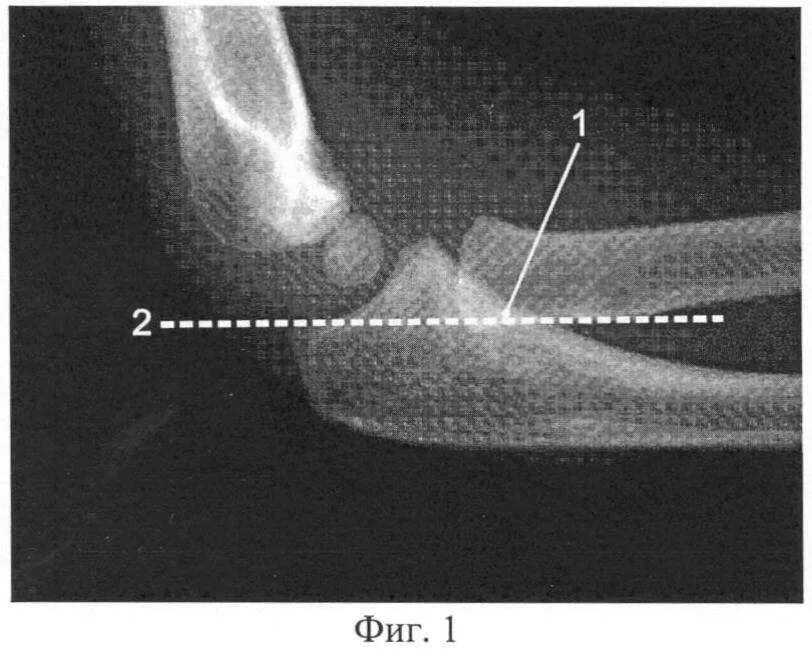

Подвывих локтевого сустава у ребенка